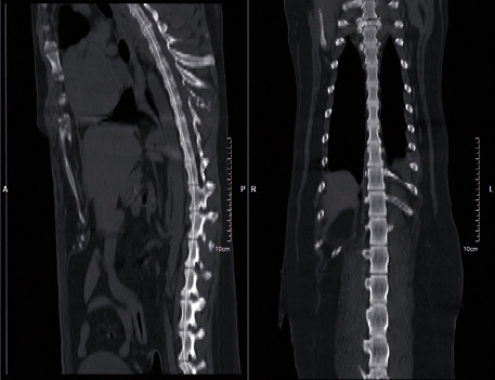

APLICAÇÕES CLINICAS